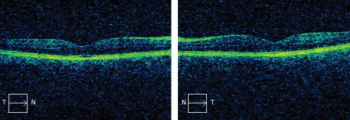

Investigators find value in screening for macular disease in preoperative evaluation